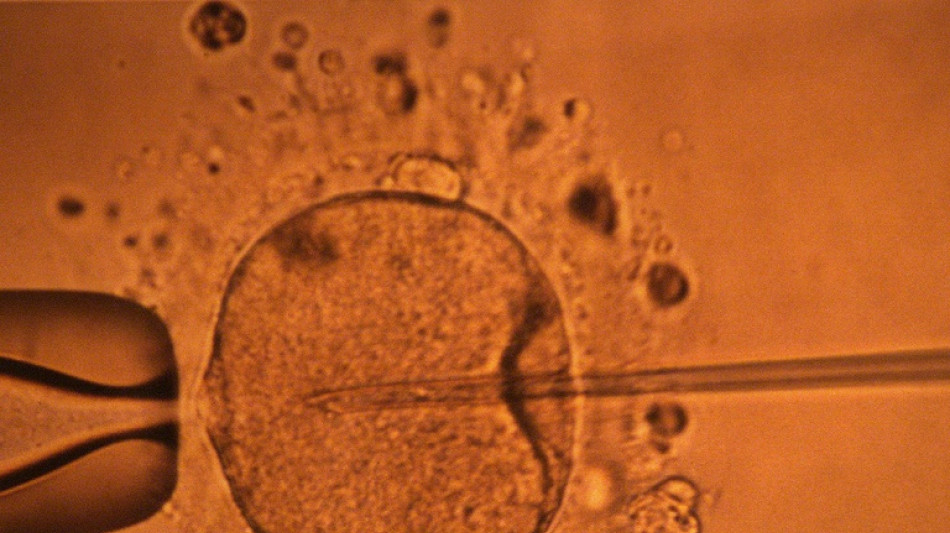

La concentración de espermatozoides, uno de los factores de la fertilidad masculina, disminuyó significativamente en todo el planeta en las últimas décadas, según un estudio publicado el martes.

La cantidad de espermatozoides es uno de los factores que afectan a la fertilidad masculina, pero no es el único.

Su movilidad también desempeña un papel crucial, pero esta característica no se mide en este estudio. Por ello, no se puede concluir que haya una disminución general de la fertilidad masculina, aunque la investigación aporta elementos en este sentido y se suma a otros trabajos que estudiaron las causas de esta tendencia.